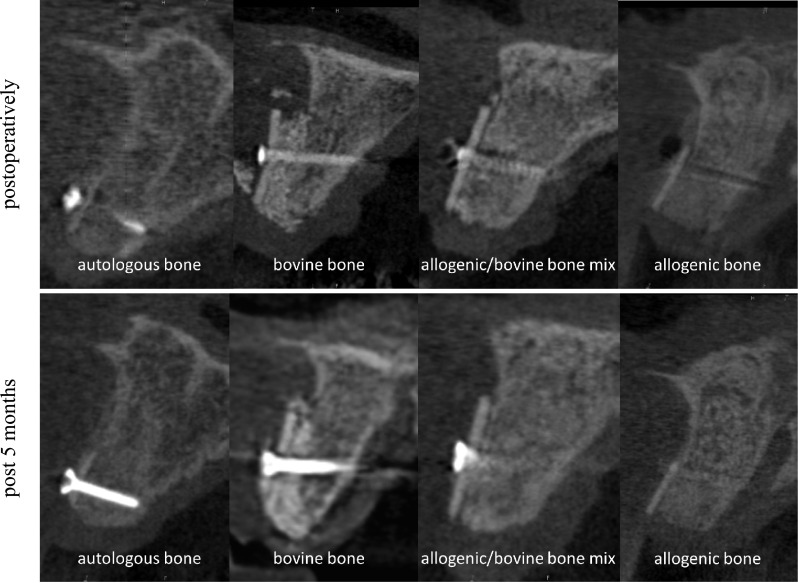

Filling the space between CP and local bone is comparable with filling defects in the context of guided bone regeneration (GBR). There are differences between the barrier function of CP and the membranes used for GBR as CP has a high-volume stability and is rigidly connected to the alveolar bone. Overall, space between CP and local bone can be filled in different ways. CBCT scans demonstrated the complete remodeling of autogenous and allogeneic granules after 5 months radiologically. On the contrary, bovine BS seems to be integrated, but radiological remodeling seems to be less compared to autogenous and allogeneic granules. On the contrary, the combination of allogeneic and bovine bone granules demonstrates a sufficient integration and partial remodeling in part with inclusion of bovine BS radiologically (Fig. 7). Up to date, detailed studies about the filling materials are missing, especially after loss to the CP. With respect to CBCT scans, use of autogenous and allogeneic granules can be recommended, especially since both groups demonstrate a complete remodeling process [44].

Fig. 7.

Alveolar ridge augmentation with different fillings, autologous bone, bovine substitute, a mixture of allogeneic bone and bovine substitute, and allogeneic bone at CBCT scans. Upper line situation postoperatively and lower line situation after 5 months in CBCT scans